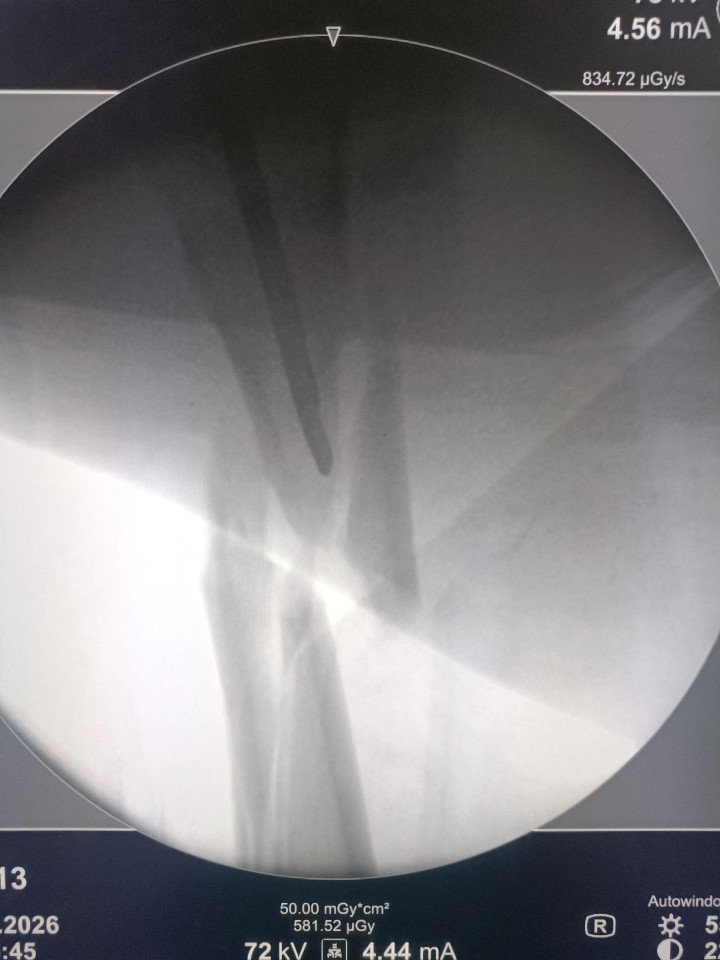

中股网 外伤导致的股骨上段骨折闭合复位股骨重建钉固定,期待早期愈合